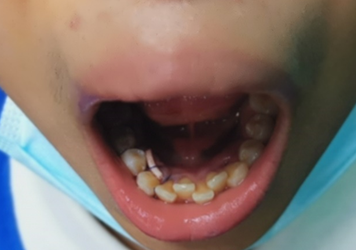

接下来以图片形式展示一例笔者最近处理的下颌骨埋伏多生牙病例,该患者下颌骨有四个埋伏多生牙,左右侧各有两个,因矫正牙齿需要要求拔除。

图8 左侧下颌埋伏多生牙手术切口及拔除后骨腔

图9 拔除的左下颌埋伏多生牙2个,其中1个为分块取出

图10 左下颌埋伏多生牙术后缝合情况,伤口置橡皮引流条

图11 右侧下颌埋伏多生牙手术切口及拔除后的骨腔

图12 拔除的右下颌埋伏多生牙2个

图13 右下颌埋伏多生牙术后缝合情况,伤口置橡皮引流条